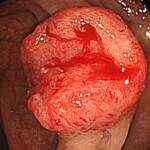

@半年前、便潜血が陰性だった進行大腸がん

@便潜血陽性を数年放置したのちに発見された進行大腸がん